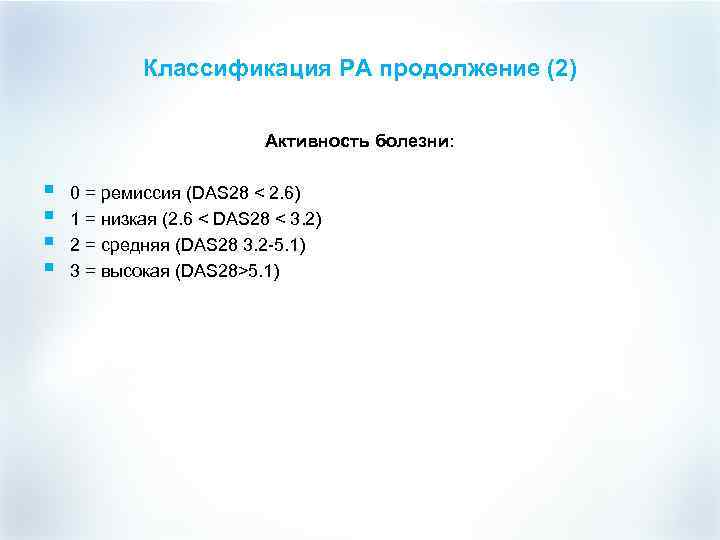

Классификация РА продолжение (2) Активность болезни: § § 0 = ремиссия (DAS 28 < 2. 6) 1 = низкая (2. 6 < DAS 28 < 3. 2) 2 = средняя (DAS 28 3. 2 -5. 1) 3 = высокая (DAS 28>5. 1)

Классификация РА продолжение (2) Активность болезни: § § 0 = ремиссия (DAS 28 < 2. 6) 1 = низкая (2. 6 < DAS 28 < 3. 2) 2 = средняя (DAS 28 3. 2 -5. 1) 3 = высокая (DAS 28>5. 1)